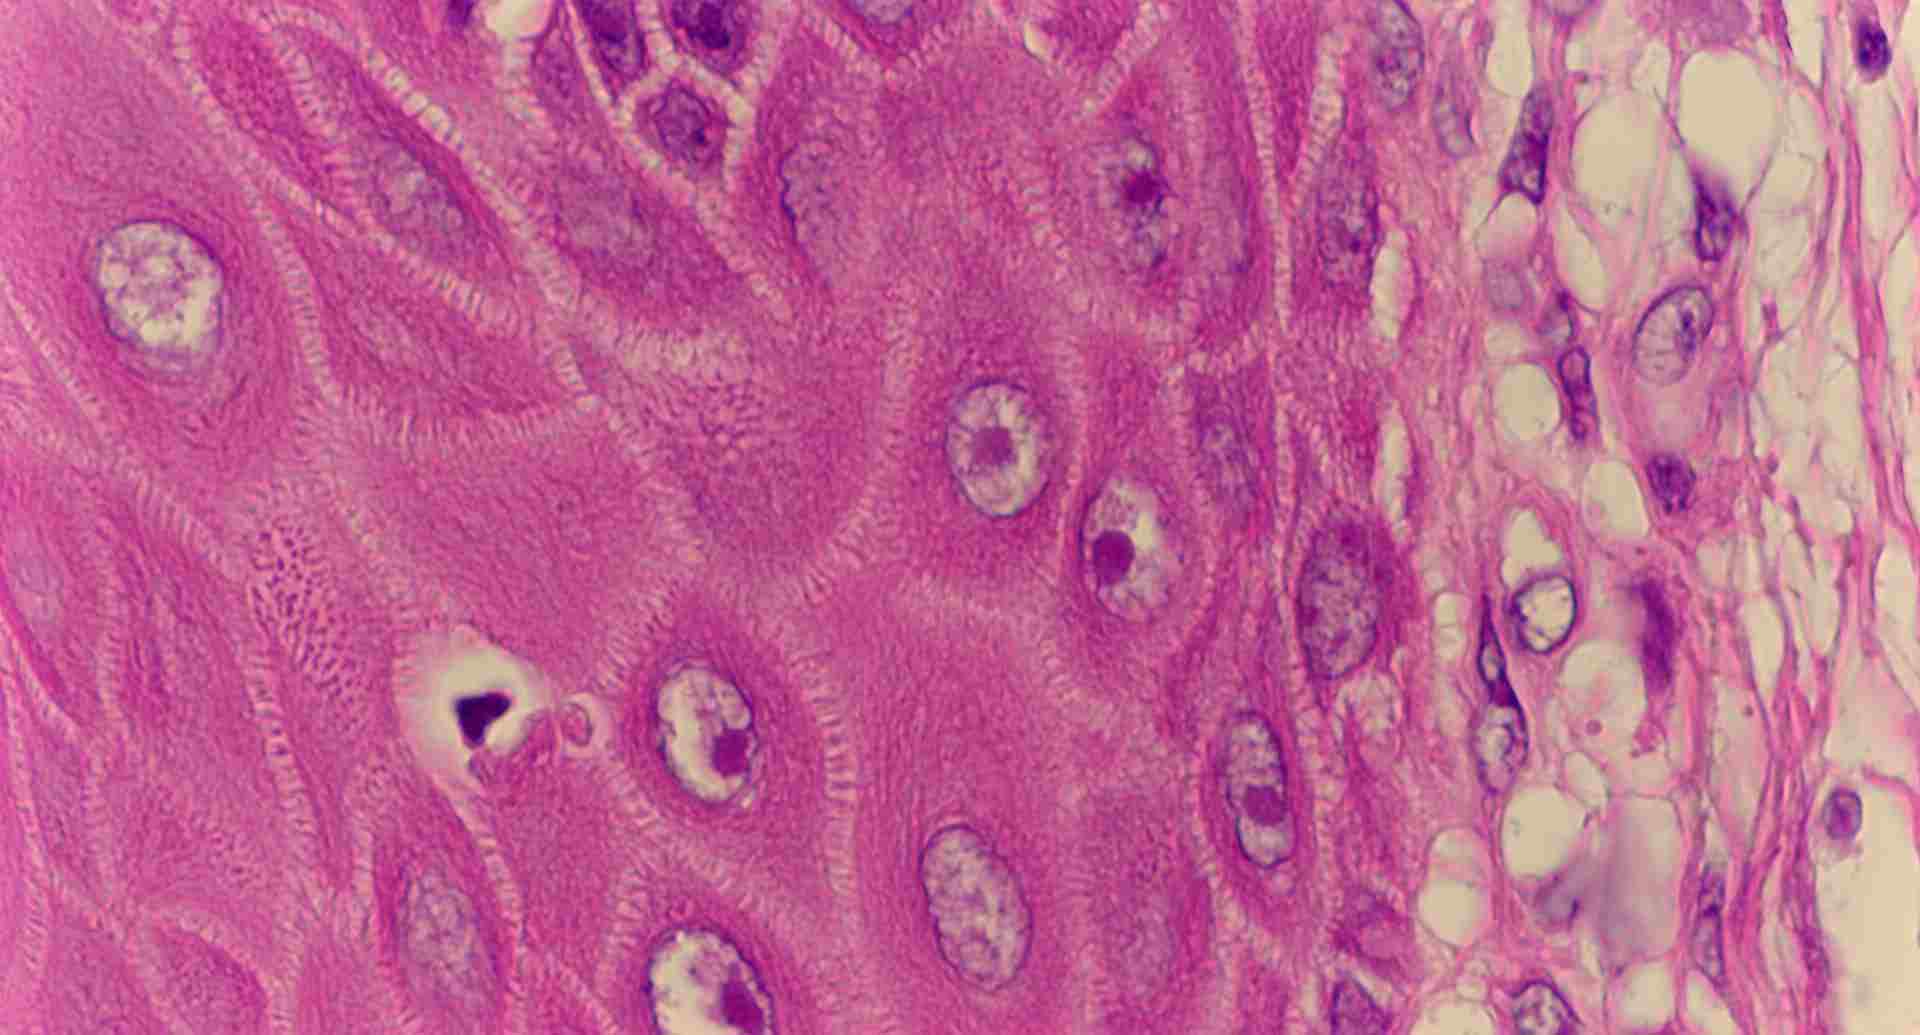

標本6

標本6の説明